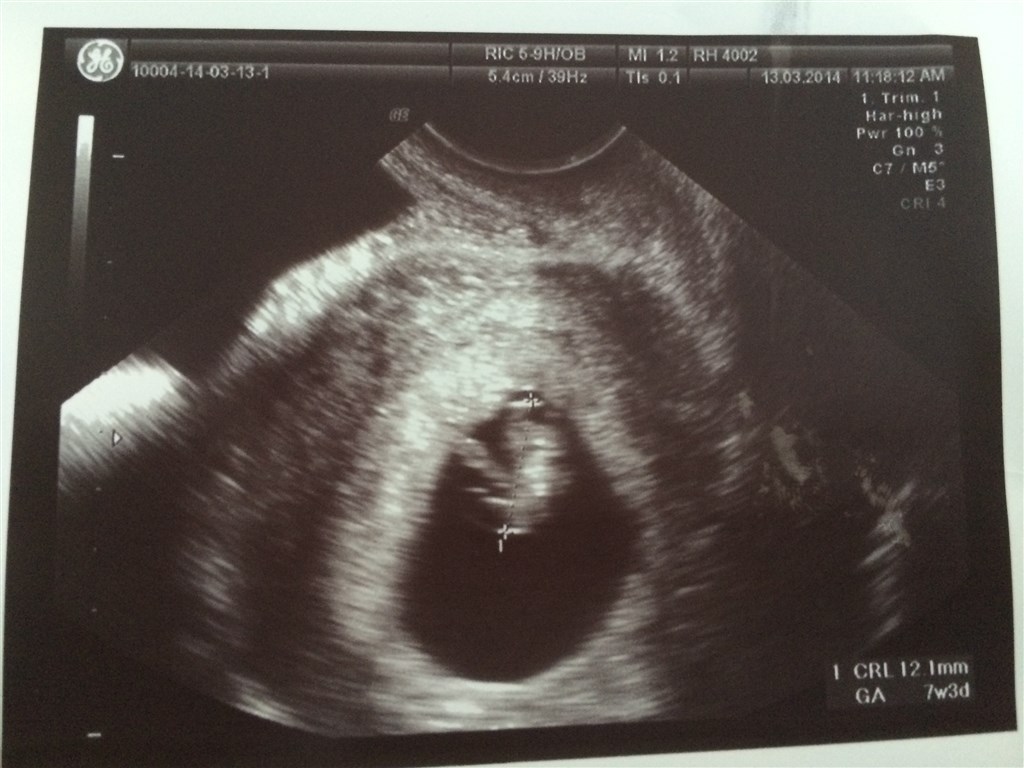

Jeg troede jeg var 8+1 i dag, men blev sat tilbage til 7+3

Det var en lang dag på RH fra 07.45-14.00 med en maaaasse snak og prøver osv osv, men det var det HELE værd da jeg for første gang så bebs lille hjerte blinke